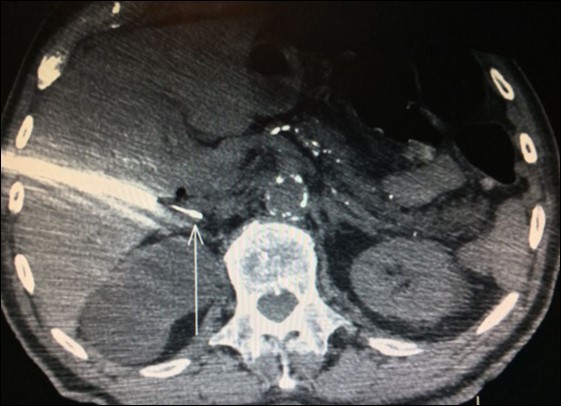

Usually, the imaging screening used for diagnosis of adrenal metastasis are: CT scans (Figure 1), magnetic resonance imaging (MRI) and PET-CT. The sensitivity of PET-CT has conflicting results, being of 96% and with false-positive detection rate even for smaller masses (without swelling and not evident on CT or MRI) of only 4% as reported in some series8,9,18. Another study confirms these findings, showing sensitivity and specificity of PET/CT for distant metastasis of 94% and 85%, respectively31.

Figure 1.CT scan showing isolated right adrenal NSLC metastasis (Arrow)